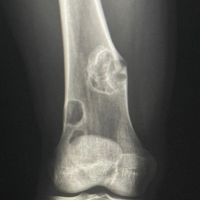

A post-operative X-ray showed the knee to be in appropriate alignment without evidence of complication (Fig. 2). The patient was transferred to the post-anesthesia care unit (PACU) in good condition, having tolerated the procedure well. Due to the patient’s high quality bone and relatively young age, a press-fit implant was chosen over the more traditional cemented implant, including: A standard width, size 8, Zimmer Persona CR Press-Fit Femoral Component, a size F, 2 peg, Press-Fit, Zimmer Persona tibial baseplate, a size 10 Zimmer Persona Medial Congruent Polyethylene Insert, and a size 38 Zimmer NexGen Press-Fit Patella. The patient continued to present for routine follow-up without evidence of complication for nearly 2 years until he returned to the clinic, stating that he had never been pleased with the operation. He complained of pain while standing, and at times, a sensation of “catching” and “giving out”. The patient underwent a normal physical exam. Three radiographic views of the left knee were examined for potential abnormalities. AP, lateral, and patellofemoral views of the left knee at this time demonstrated a failed patellar component with a shear fracture of the single peg prosthesis (Fig. 3). These findings were shared and discussed with the patient, who agreed to proceed with revision of the patellar component.

Figure 3: Second post-operative X-rays. Three views of the left knee are visualized at this post-operative visit, including anteroposterior, lateral, and patellofemoral views, respectively. These radiographs demonstrate a broken patellar component with a shear fracture of the single peg prosthesis. The femoral and tibial components appear well fixed and positioned.